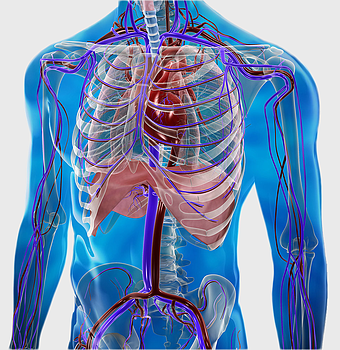

human circulatory system, blood vessel anatomy, weight loss exercise benefits, heart and artery health, vascular network visualization, cardiovascular health illustration, systemic circulation diagram -

red vascular network illustration, blood vessel line art, human body circulatory system, thrombus medical graphic, anatomical red vein depiction, cardiovascular disease diagram, artery and vein branching++) -

heart anatomy illustration, cardiovascular system diagram, circulatory system medical, vascular system sonography, human body blood flow, arterial network visualization, heart function analysis -

human circulatory system diagram, blood vessel network illustration, human anatomy chart, cardiovascular system overview, human body medical illustration, physiological system depiction, organ function visualization -

circulatory system anatomy, omega-3 fatty acids benefits, cardiovascular health, medical illustration, human body vascular network, blood vessel visualization, heart function diagram -